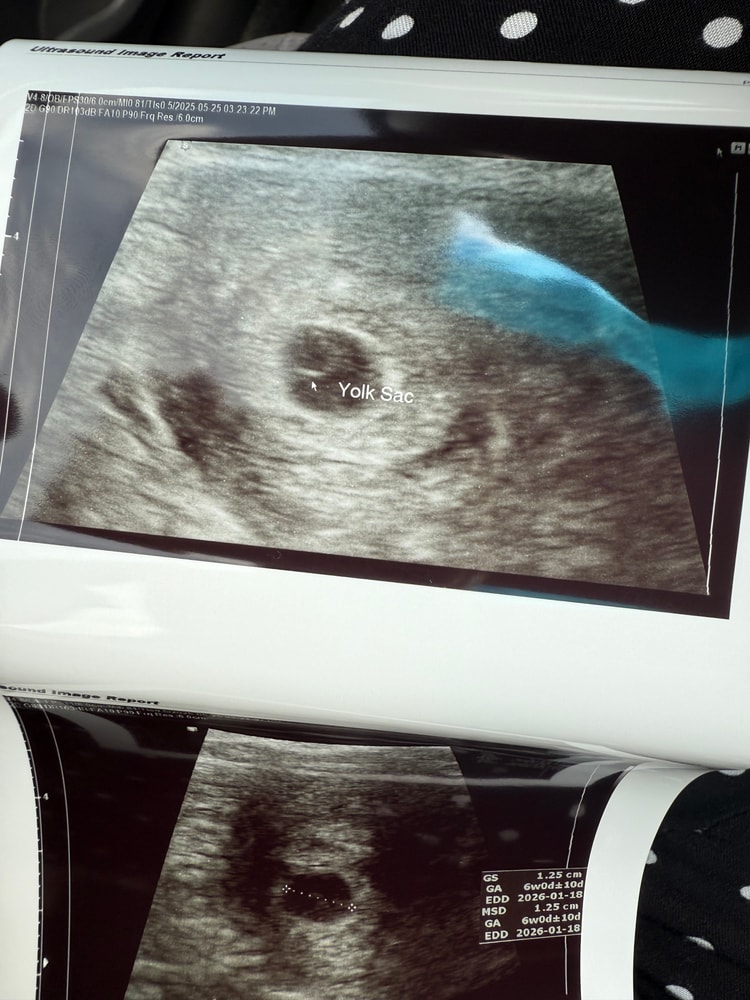

Вторая и последующие беременностиЛовлю «флэшбэки», после третьего и наконец удачного переноса родила мальчишку, ему уже 1,4 и воооотт на днях узнала , что беременна . С одной стороны не могу поверить , что со мной такое чудо произошло (бесплатно😅) , но в то же время снова переживания , место себе не нахожу . Побежала на узи , поставили срок 6 недель ровно , НО ! Есть плодное яйцо и желточный мешочек , а эмбриона и сердцебиения пока не видно и не слышно … отправили гулять 2 недели . Скажите , есть шанс , что просто рано побежала на узи или например , что на таком маленьком сроке лучше трансвагинальное узи делать , оно более точно показывает ?У кого было похожее ?

У меня на таком сроке в ЖК через живот даже плодное яйцо не нашли. Сказали приходить через неделю для подтверждения беременности.

А я не выдержала и пошла и сделала платно трансвагинально. И там уже все увидели. Но сердце даже таким способом только через неделю услышали

У меня только в 7 недель ровно нашли. В 6 недель был только жм, а в 7 пришла, а на экране уже такая креветочка была и сердечко)))

У меня в эту беременность в 6,3 эмбрион 3,6мм и пульсацию только увидели, через 3 дня на узи эмбрион уже 5мм и сб 142уд было)